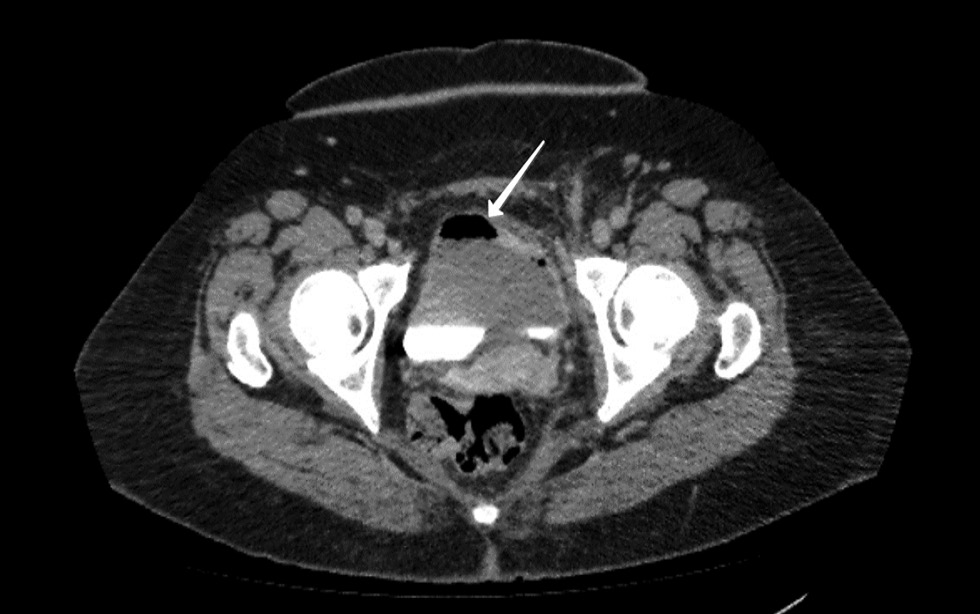

В левой паховой области определяется инфильтрат аксиальным размером 34 × 21 мм, с нечеткими контурами и наличием воздуха в центре (рис. 5). Инфильтрат интимно прилежит к левой прямой мышце живота, утолщенной. В заключении исследования подтверждены косвенные КТ-признаки пузырно-кишечного свища.

Рис. 5. Компьютерная томография органов брюшной полости. Маркирован инфильтрат в полости малого таза

Fig. 5. Computed tomography of the abdomen. Infiltrate in the pelvic cavity is indicated